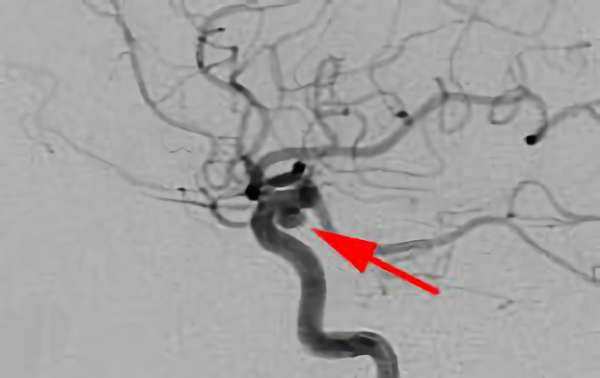

No.1628 手術前